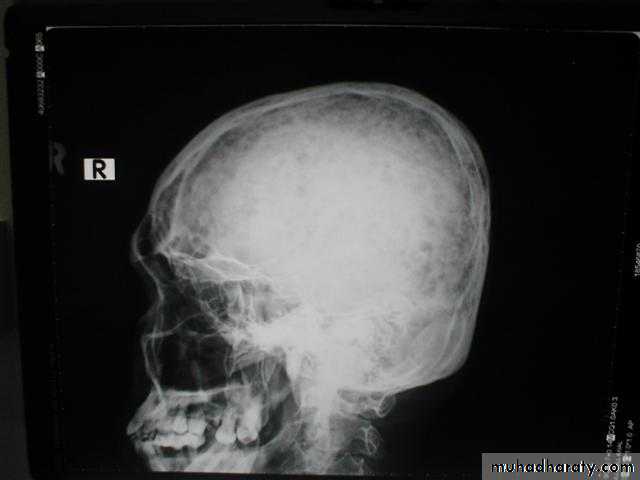

Primary hyperparathyroidism(Radiological features)

Characteristic changes on plane X ray are:

Demineralization, subperiosteal erosion and resorption of terminal phalanges

Pepper pot appearance of the lateral X ray of the skull

Scattered opacities within the renal outline (nephrocalcinosis)

renal stones

Soft tissue calcification affecting arterial walls, hands or cornea

Chondrocalcinosis